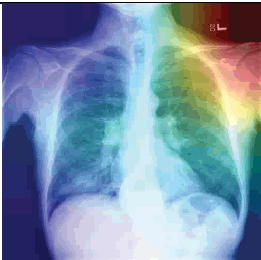

우리에게 굉장히 적은 데이터들이 주어졌을 때, supervised learning을 적용한다면 흔히 overfitting 문제가 발생할 것입니다. 예를 들어, 우리에게 아래와 같은 Chest X-Ray 폐렴 데이터만 갖고 있다고 해보겠습니다.

이미지 출처:https://www.openaccessjournals.com/articles/advanced-neural-network-solution-for-detection-of-lung-pathology-and-foreign-body-on-chest-plain-radiographs-13104.html

그림 출처:https://www.openaccessjournals.com/articles/advanced-neural-network-solution-for-detection-of-lung-pathology-and-foreign-body-on-chest-plain-radiographs-13104.html

의사들이 보는 폐렴 증상은 분명 폐주위의 섬유화에 주목하겠지만, 딥러닝의 경우는 CAM(=Class Activation Map)을 통해 살펴보면 엉뚱한데주목하는 경향이 있습니다. 아래와 같이 엉뚱한 곳을 보는 이유폐렴 관련 데이터는 저런 부분들만 살펴봐도 분류가 가능했기 때문일 수 있습니다. 즉, 정답의 이유는 상관없이 "학습 데이터의 정답만 맞추면 된다"는 식인 것이죠.

하지만, 저런 artifacts와 같은 요소들이 없는 폐렴 데이터가 들어오면 곧 바로 틀려버립니다. 즉, supervsied learning 방식을 사용한 CNN적은 수 의 폐렴 데이터로 학습하게 되면, 폐렴 CXR 이미지를 제대로 representation 해줄 수 없게 된다고 이야기 할 수 있습니다.